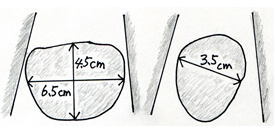

また前立腺のおおよその大きさ・形状と合わせて残尿をみるにはエコー検査が極めて有用です。尿を十分に溜めた状態で恥骨上にプローベを当てれば(高度の肥満症例でない限り)、前立腺の形状を概ね理解することができますし、時には膀胱内病変(腫瘍や結石)の診断にも有用です。また排尿後には残尿も測定可能でありこれにより大まかな排尿状態の理解が可能となります。前立腺体積、残容量ともに3方向を計測し0.55を乗ずることで回転楕円体に近似した体積が測定できます。薬剤治療にもかかわらず症状の改善されない方、あるいは前立腺体積が30ml以上、残尿が50ml以上が続くような場合は一度は泌尿器科の診察を受けられるのがよいかと存じます。体積の測定は3方向を測定し a x b x c x 0.55cm3 で計算する。(図の残尿であれば6.5 x 4.5 x 3.5 x 0.55=65.3ml)

残尿量の測定